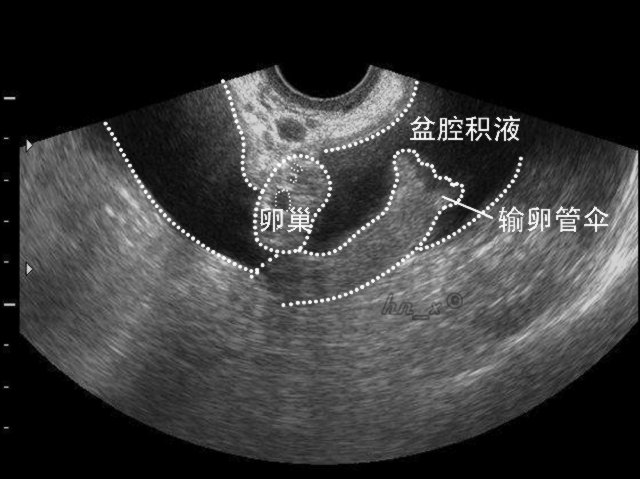

盆腔积液的病因:

因为盆腔是腹腔在全身最低的部位,当有渗出液或漏出液时都会引流到盆腔,从而形成盆腔积液。部分正常妇女在月经期或排卵期会有少量血液聚积在盆腔,形成盆腔积液,这种情况无需治疗。在临床上大多数妇女的盆腔积液是由于炎症引起,是盆腔存在炎性渗出物。